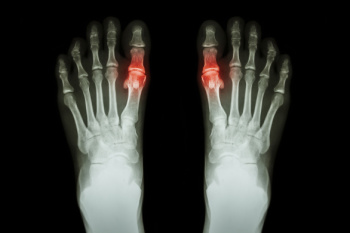

Turf toe is a sprain of the main joint at the base of the big toe, usually caused by excessive upward bending of the toe. It often happens in athletes who play on artificial turf, where the surface grips the foot too firmly during sudden starts or stops. Wearing flexible shoes that allow too much toe movement can also increase the risk. The condition develops when the big toe is forced beyond its normal range of motion, stretching or tearing the ligaments that stabilize the joint. This can occur from pushing off forcefully, landing awkwardly, or direct impact during sports. Symptoms include pain, swelling, and stiffness at the toe joint, which may worsen with activity. If you experience persistent toe pain or swelling after a sports injury, it is suggested that you see a podiatrist for a proper diagnosis and appropriate treatment.

Diagnosis

Due to the wide variety of potential causes of ankle pain, podiatrists will utilize a number of different methods to properly diagnose ankle pain. This can include asking for personal and family medical histories and of any recent injuries. Further diagnosis may include sensation tests, a physical examination, and potentially x-rays or other imaging tests.